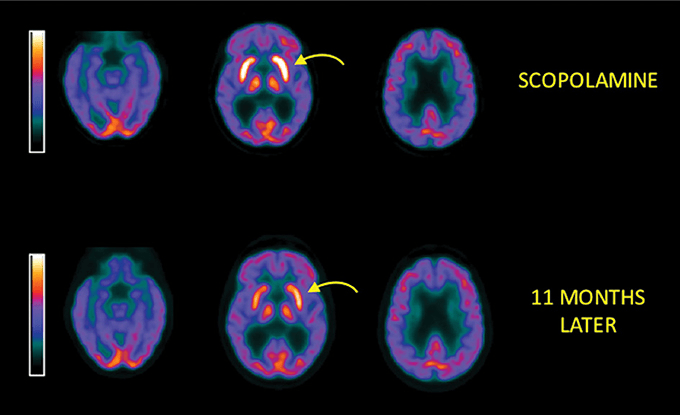

Ως αντιχολινεργικό φάρμακο, η σκοπολαμίνη μπλοκάρει τον νευροδιαβιβαστή ακετυλοχολίνη, ο οποίος παίζει βασικό ρόλο στη μνήμη, τη μάθηση και τον συντονισμό. Αυτός ο αποκλεισμός βοηθά στη μείωση της ναυτίας διαταράσσοντας τα σήματα από το σύστημα ισορροπίας προς τον εγκέφαλο. Ωστόσο, έχει και παρενέργειες, ειδικά όταν χρησιμοποιείται σε υψηλές δόσεις ή εκτός κλινικού περιβάλλοντος. Το γεγονός ότι διαταράσσει το χολινεργικό σύστημα, το οποίο είναι κρίσιμο για τη διαμόρφωση και ανάκτηση της μνήμης, ως αποτέλεσμα, μπορεί να προκαλέσει προσωρινή αλλά σοβαρή απώλεια μνήμης και γενικά διαταραχές και σε άλλες γνωστική λειτουργία. Η δύναμη της να «διαγράφει« τη μνήμη, περιγράφεται συχνά ως «ζομποποίηση«, κάνοντάς την αντικείμενο εγκληματικής και ιατροδικαστικής έρευνας. Τα θύματα συχνά περιγράφουν σύγχυση, παραισθήσεις και πλήρη απώλεια ελέγχου.